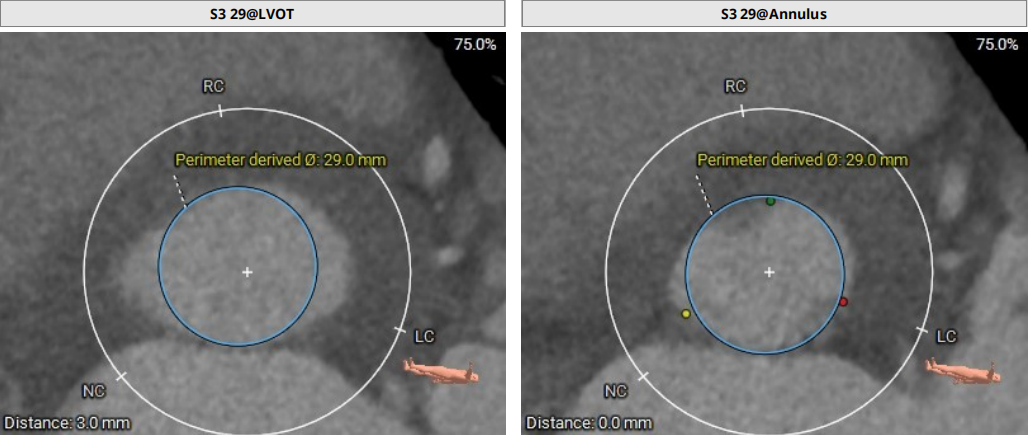

模拟29mm瓣膜植入情况:

79岁男性患者,主动脉瓣狭窄伴反流,主动脉瓣环面积约741mm²,折算瓣环直径30.7 mm,LVOT约958mm²,折算直径34.9mm,冠脉堵塞风险低,窦部空间可,瓣环夹角60°,EF值极低,心功能极差,属于终末期心衰患者。经手术团队综合评估,患者属于超大瓣环,已接近S3球扩瓣的直径上限,谨慎评估锚定区间,考虑瓣叶增厚以及交接融合因素,团队认为球扩瓣强径向支撑力可以锚定;术前患者EF较低,心力衰竭,多瓣膜反流,需要尽量减少操作,快速植入瓣膜,拟在植入ECMO的情况下以右侧股动脉为主入路行经导管TAVR,术中拟植入29#SAPIEN3瓣膜,考虑到瓣环面积超过29瓣膜适用的上限,术中拟+4cc直接释放,于80/20,实现瓣上锚定,视情况选择是否后扩。

78岁男性患者,主动脉瓣重度反流,瓣环面积约578.0mm²,折算瓣环直径27.1mm,LVOT约618.8mn折算直径28.1mm,轻度横位心,腹主动脉-降主动脉段迂曲,同时合并心功能不全,肺癌手术,属于外手术风险高危患者。经手术团队综合评估,患者为纯反流病例,瓣叶增厚并不明显且LOVT面积更大,仅瓣叶交界有少量钙化,对瓣膜锚定径向支撑力的要求很高,经过团队反复讨论,实施模拟分析后,拟行经导管TAVR术,拟以右侧股动脉为主入路,拟入29#SAPIEN3瓣膜,术中拟+3cc释放来实现oversize22%,于80/20位置释放,通过瓣环和瓣交接钙化实现瓣膜锚定,视情况选择是否后扩。